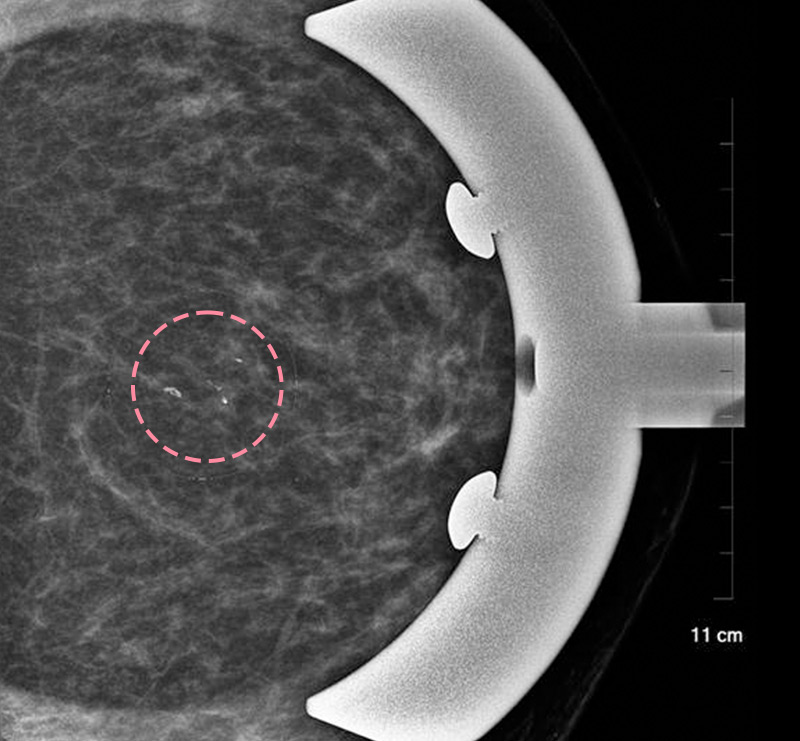

맘모톰시술 후 병리조직검사에서 상피내암(조기유방암)으로 진단되어 대학병원으로 연계해 드린 환자분의 사례입니다. 암을 초기 단계에 찾음으로써 항암치료 없이 간단한 수술을 통해 치료가 가능하였습니다.